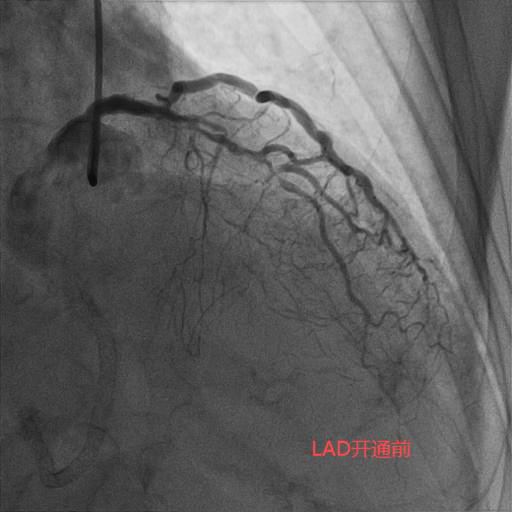

今年83岁高龄的刘老先生,退休前从事地质工作,平素身体硬朗,但近期发现快走后出现憋气症状,到某医院就诊,冠状动脉造影检查为三支病变,前降支(LAD)、回旋支(LCX)、右冠状动脉(RCA)均为完全闭塞病变且伴重度钙化。在经过近一个小时的尝试后,闭塞血管未开通,建议药物治疗。但药物治疗并未缓解刘老先生的症状,心功能反而一步步下降。后来患者及家属抱着极大的期望去某著名心脏专科医院就诊,经过半个小时的尝试后开通失败,并告知患者家属这样的血管不可能开通,冠状动脉搭桥术是唯一的出路。但是搭桥手术对于一位83岁高龄的老人来说无疑是一个艰难巨大的挑战。两次失败手术的打击使得刘老先生的身体状态每况愈下,稍事活动就气喘吁吁,逐渐对生活失去了信心。后来家属辗转打听到北京潞河医院心内科翟光耀主任团队致力于冠状动脉复杂手术,抱着最后一搏的想法,在经过两个月的药物调整后能耐受再次手术的前提下,刘老先生再次躺在了手术台上。术中,冠状动脉造影结果让翟光耀主任团队意识到了这次手术的难度之大,风险之高。三支主干闭塞,之前手术开通失败已造成血管近端夹层,闭塞的血管(尤其是RCA)全程重度钙化,近乎全程闭塞,开通血管无疑在花岗岩上开凿隧道。在经过近4个小时的不懈努力,团队终于成功开通了难度最大的RCA并植入支架,观察一天后顺利出院。 一个月后,刘老先生闭塞的LAD也成功开通。现在,刘老先生身体恢复良好,如获新生!